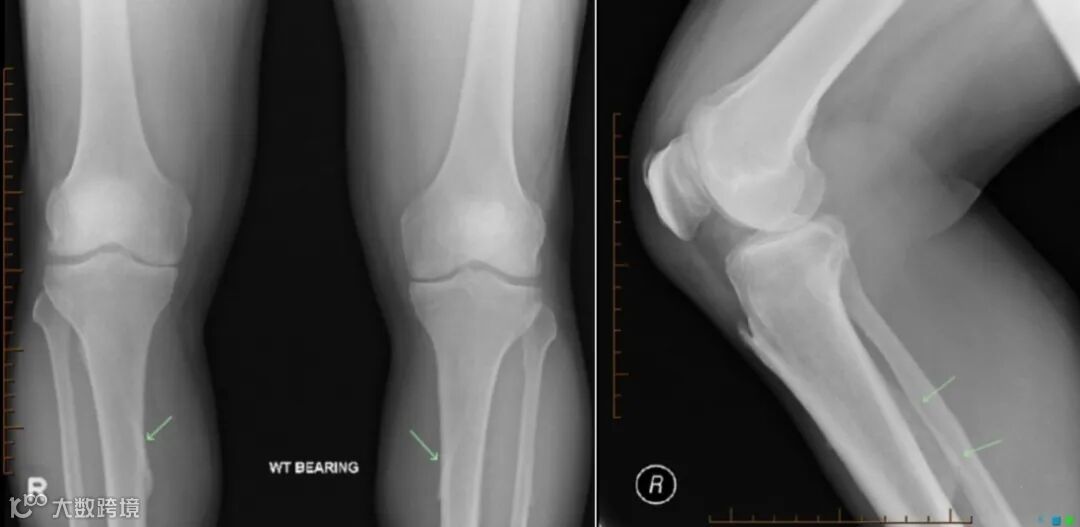

图1.双侧胫骨可见对称性的由胫骨背侧近端、斜向内下走形的硬化带,为“比目鱼肌线”。

图2 双侧比目鱼线,侧位显示不明显。